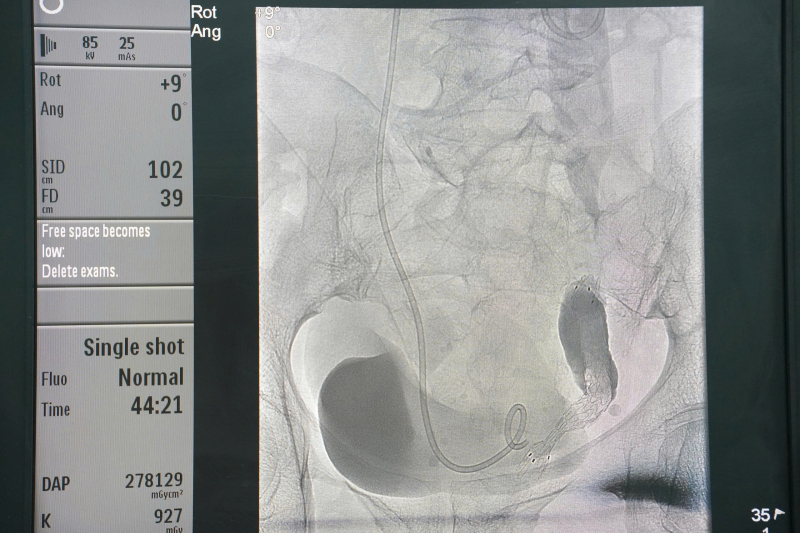

Hình ảnh: stent niệu quản trên hệ thống chụp mạch số hóa xóa nền (DSA).

Kỹ thuật được chỉ định cho các trường hợp tắc nghẽn đường bài xuất tiết niệu gây giãn đài bể thận, có thể do u xâm lấn hay chèn ép làm hẹp niệu quản hoặc sỏi … và các bệnh nhân này không thể đặt sonde JJ theo đường ngược dòng. Dưới sự hỗ trợ của hệ thống DSA hiện đại, bác sĩ can thiệp tiếp cận bể thận qua da, đưa stent niệu quản hoặc sonde JJ chính xác, an toàn, giúp giải phóng tắc nghẽn, bảo tồn chức năng thận và cải thiện nhanh tình trạng người bệnh.